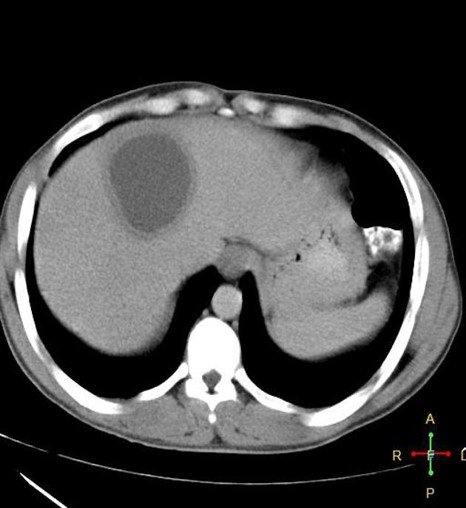

Contrast-enhanced computed tomography of a 15-year-old female presenting with abdominal pain showing a well-circumscribed, unilocular, non-enhanced cystic lesion in the right lobe of the liver with typical “double-wall sign” of hydatid cyst (arrows).

Cyst in the liver with daughter cyst.